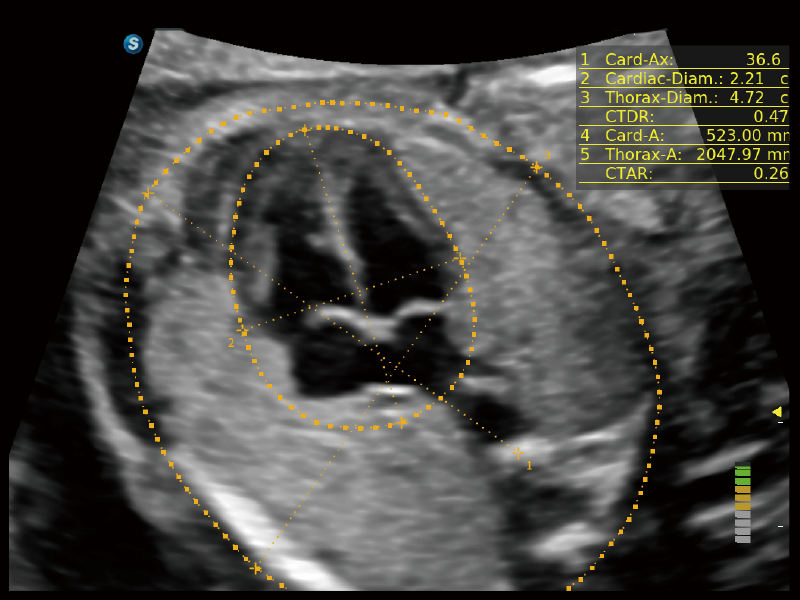

作為開(kāi)立醫(yī)療全新打造的超高端旗艦超聲產(chǎn)品,從探頭抬起喚醒開(kāi)啟掃查到多維探頭發(fā)射接收,通過(guò)先進(jìn)的場(chǎng)成像發(fā)射、自適應(yīng)聚合重建等技術(shù),基于RF Data原始射頻數(shù)據(jù)在圖像生成、高端功能等方面實(shí)現(xiàn)突破,為婦產(chǎn)科、兒科提供全方位臨床解決方案。

夢(mèng)溪?P80以“關(guān)愛(ài)女性”為基石,提供全方位的解決方案,量身定制以滿足女性的健康需求,涵蓋婦科、生殖健康檢查、產(chǎn)前篩查及產(chǎn)后康復(fù)等領(lǐng)域。